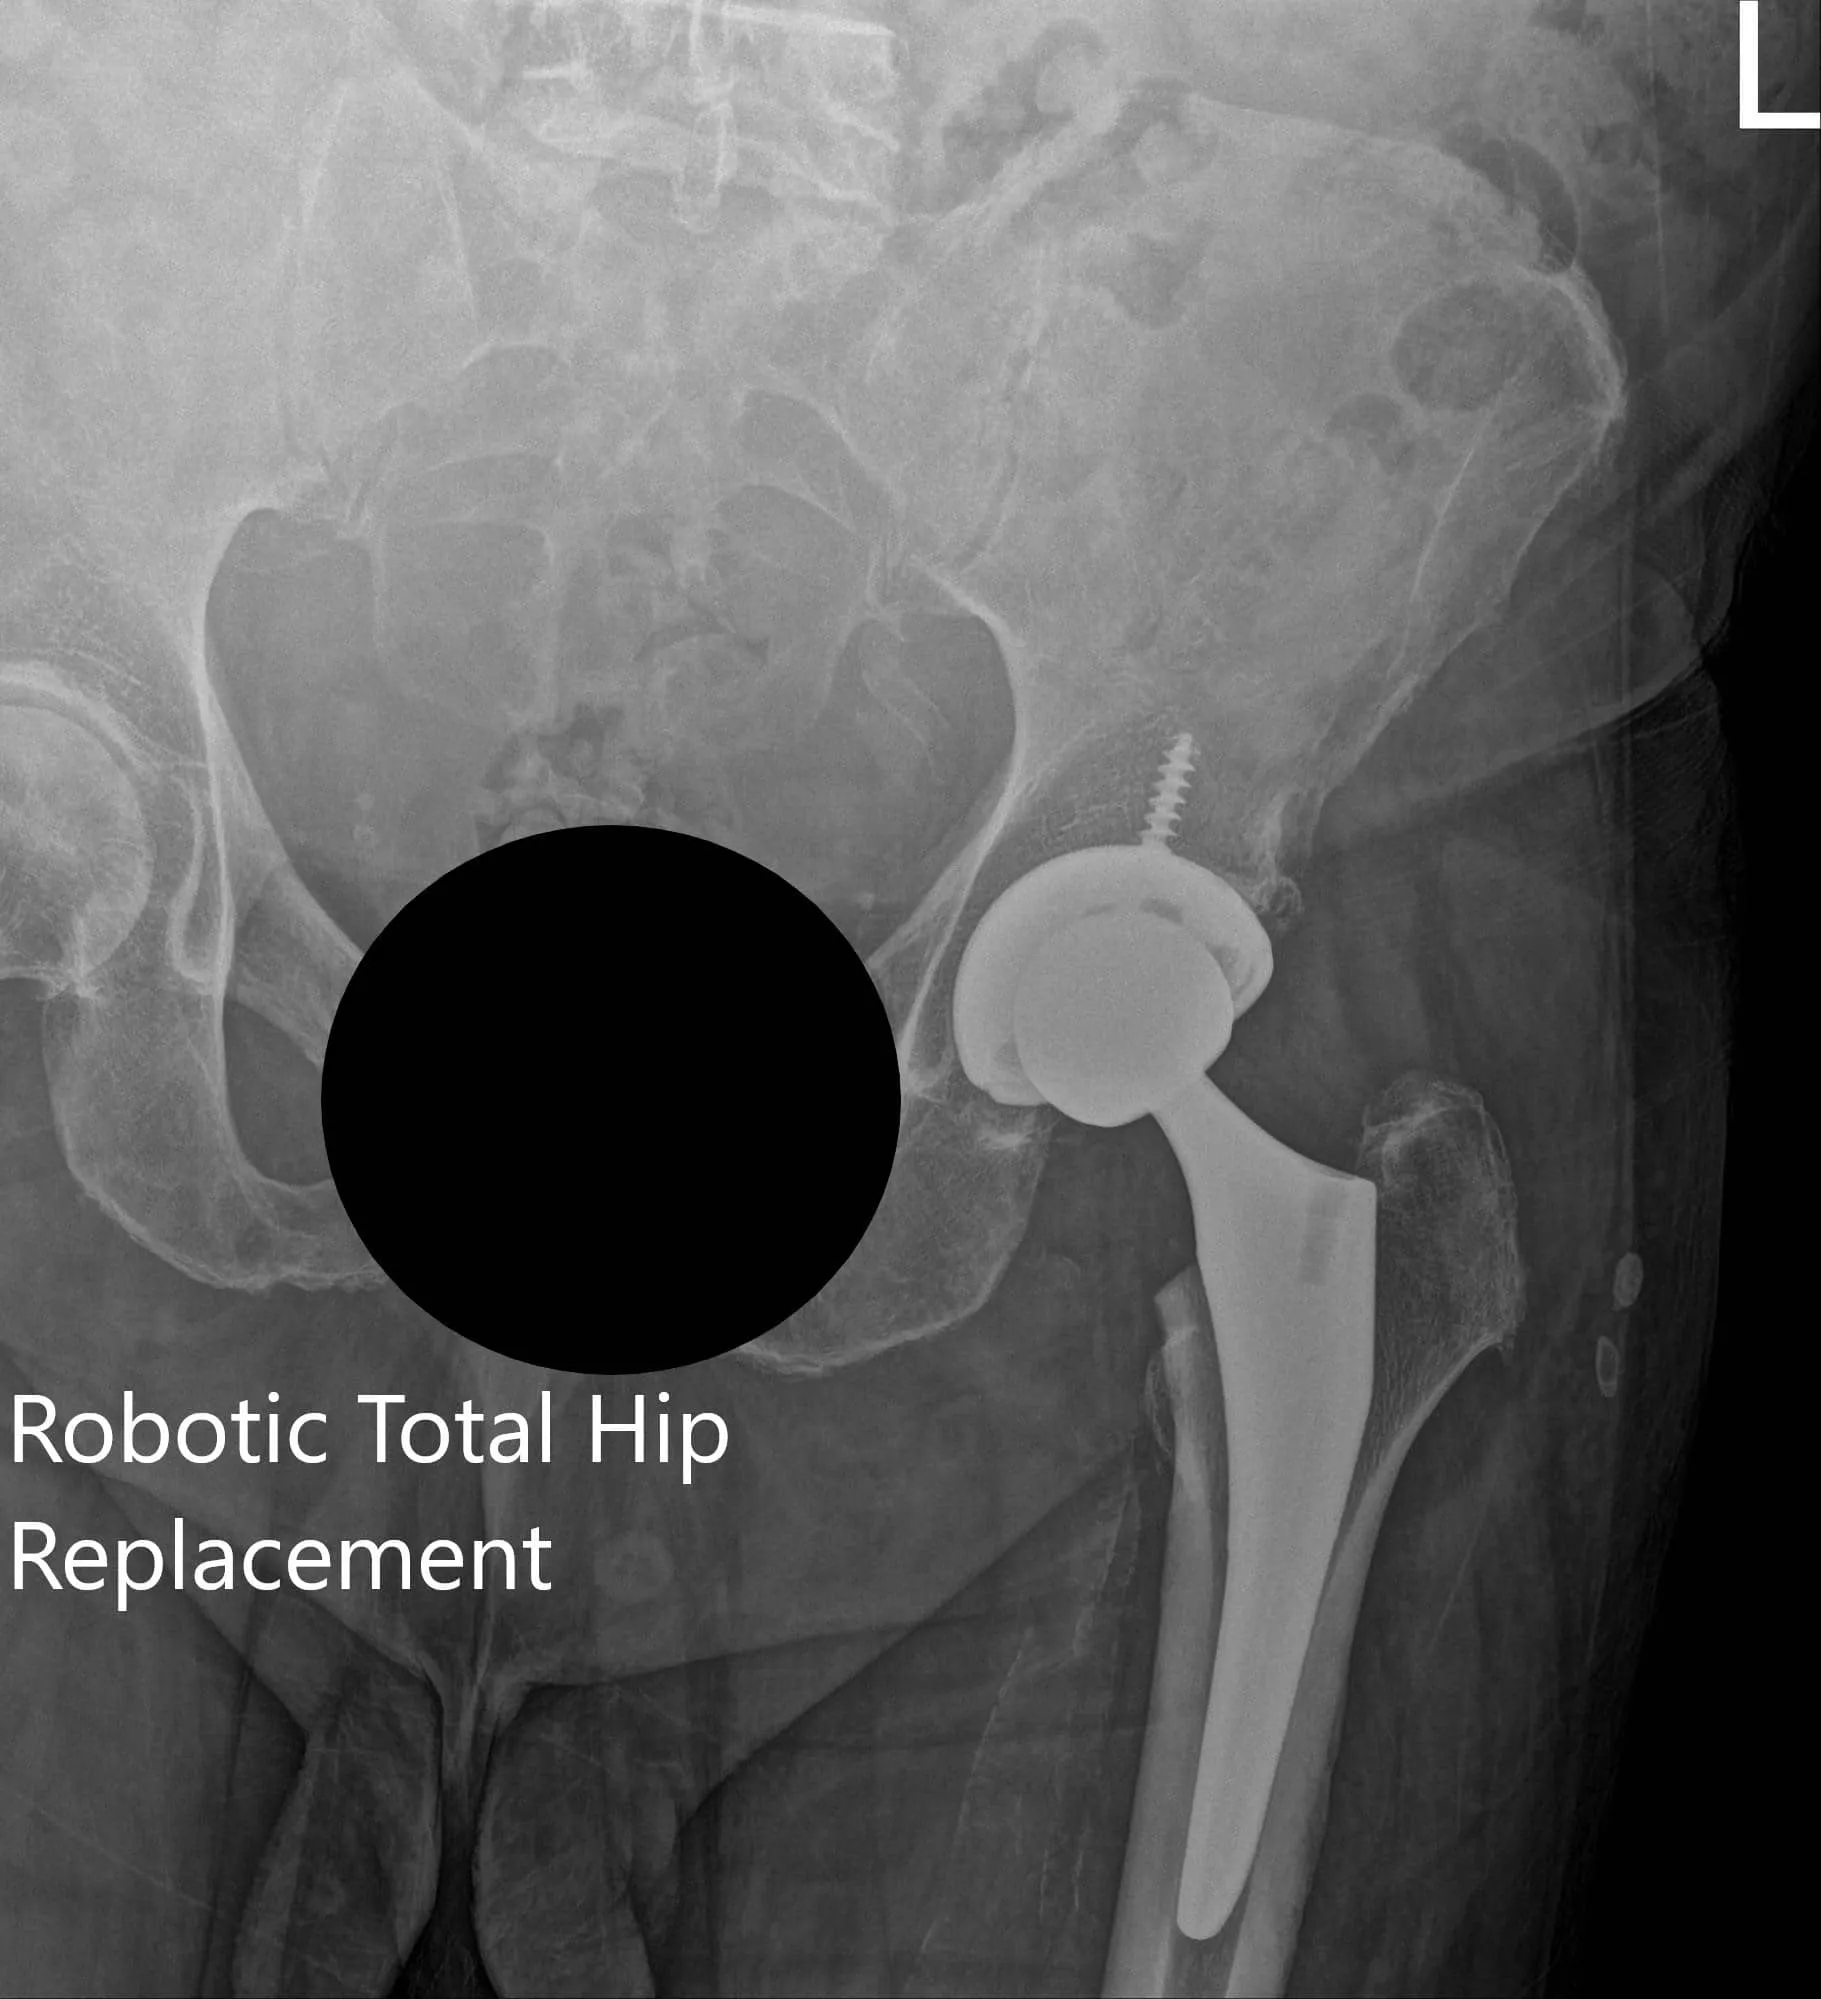

IMPLANTES UTILIZADOS: Cabeza femoral cerámica de 36 mm más 5 con sistema de vástago de cuello de 127 grados tamaño 5 con un orificio de racimo de concha acetabular de 54 mm con inserto de polietileno y tornillo de 25 mm.

Radiografía postoperatoria de la cadera izquierda que muestra visión AP y pata de rana lateral